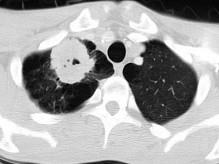

42岁,男,嗜烟酒,近1周咳嗽、咯血,请结合CT检查选择最可能的诊断 ( )A.肺结核B.肺癌C.肺曲菌病D.韦格肉芽肿E.肺错构瘤

问题 42岁,男,嗜烟酒,近1周咳嗽、咯血,请结合CT检查选择最可能的诊断 ( )

选项 A.肺结核 B.肺癌 C.肺曲菌病 D.韦格肉芽肿 E.肺错构瘤

答案 A